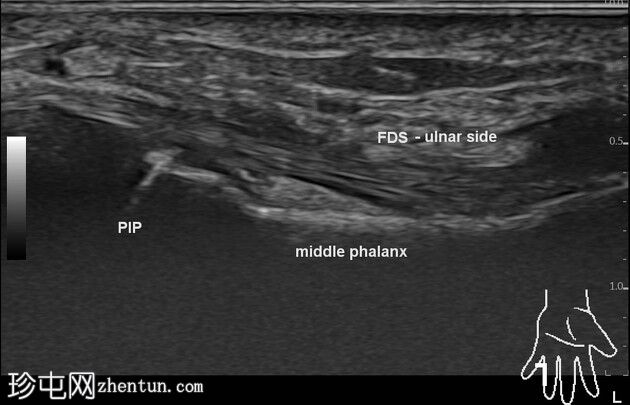

这是无名指侧位X光片。远端指骨掌侧骨性撕脱,位于中节指骨头和远端指骨干水平。远端指骨关节外骨折延伸至靠近其基底部的背侧皮质。无脱位/骨损伤。